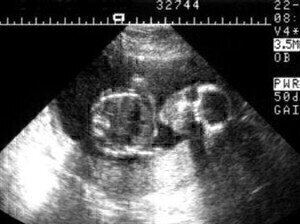

The sound they produce can be of a wavelength of less than the visible light range, potentially unlocking the door to more precise imaging using sound, rather than optical microscopes.